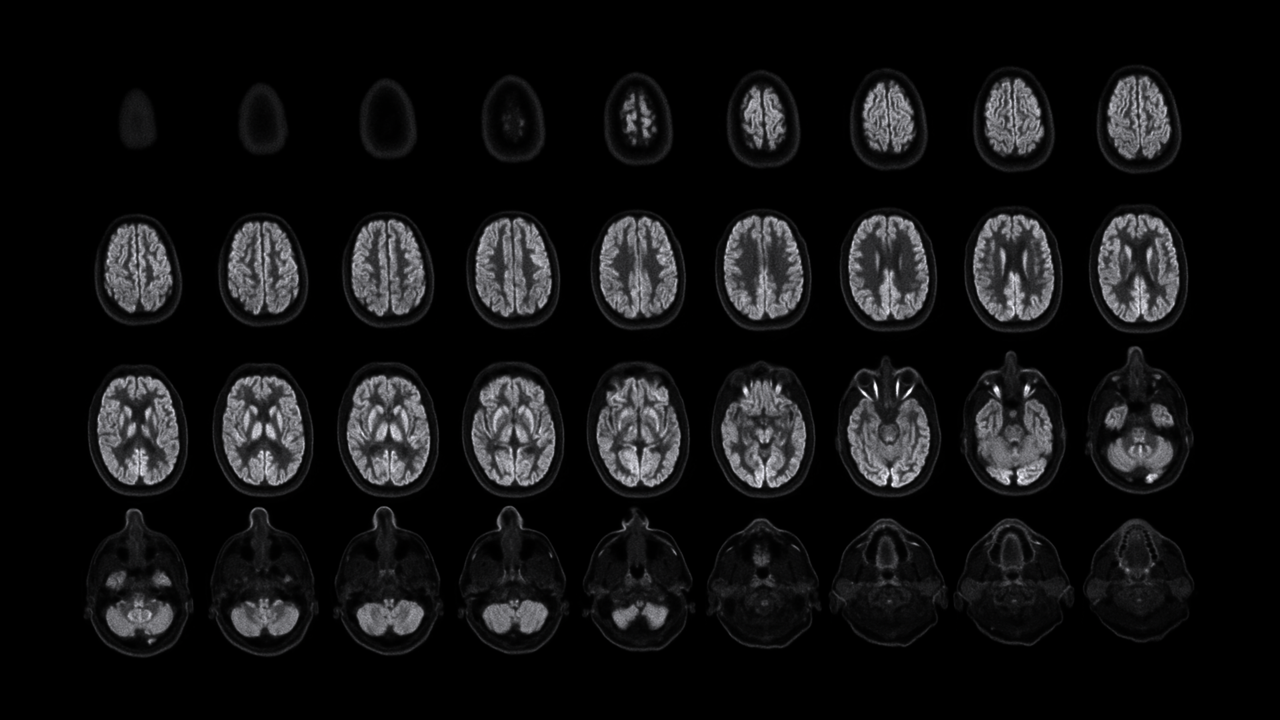

NeuroExplorer (NX)产出的脑部影像图

NeuroExplorer拥有基于NEMA NU 2-2018标准的超高灵敏度:46cps/kBq,同时配备着先进的时间飞行技术,进一步增强了NX的综合性能。

卓越空间分辨率 洞察大脑微观

小型探测器元件确保最精微的结构能被检测,甚至探查特定脑核中的神经递质运动。搭载1.5mm的有效空间分辨率,带来前所未见的解剖细节。